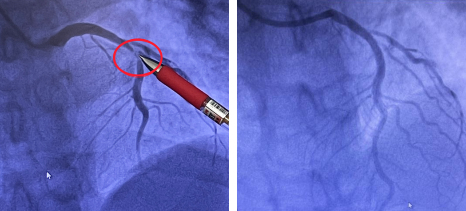

(左图)术前血管狭窄99% (右图)术后该血管通畅

与患者家属沟通后,一键启动介入手术绿色通道。术中造影发现李师傅一重要血管狭窄度高达99%,其它血管也有不同程度的狭窄,病情十分危急。必须立即对“罪犯血管”疏通,否则李师傅随时有生命危险。随着导丝通过、球囊扩张、支架植入,堵塞的血管再次通畅起来,李师傅腹痛症状缓解,脱离生命危险。